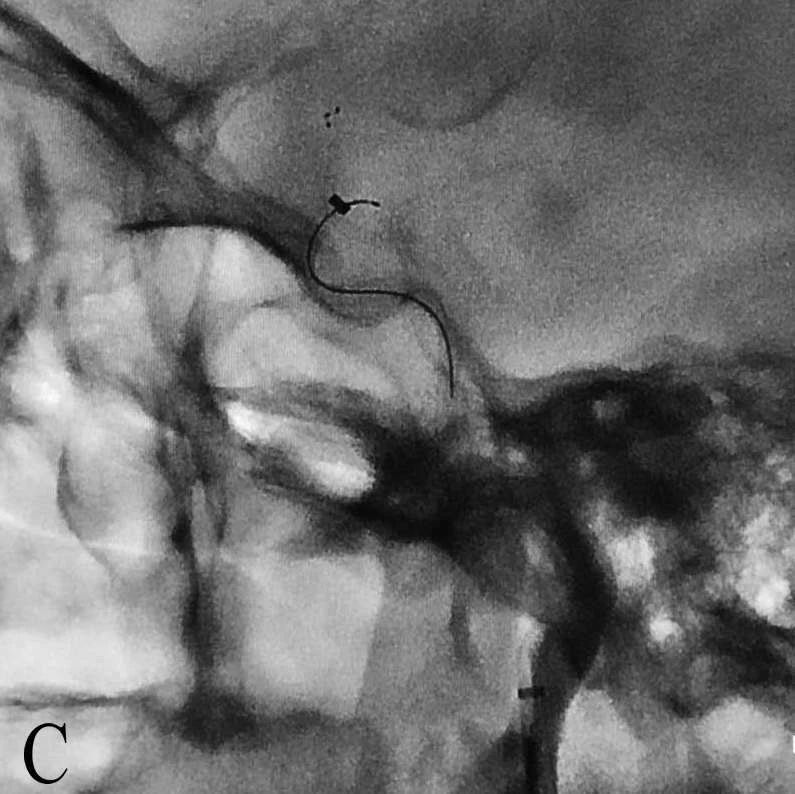

C:球囊导引导管+中间导管+支架取栓